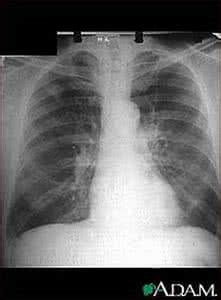

单纯照一个胸透难以检查肺癌。一般我们建议40岁以上、常年吸烟、有肿瘤家族史的肺癌高危人群每年做一次低剂量的螺旋CT,螺旋CT分辨非常高,小于4毫米结晶也能够被发现。因此,检查肺癌也是有方法的,大家并不用为此发愁。

而普通的胸透并不能直接检查肺癌,但肺部阴影能提示肺癌,若肿块比较小而且位于纵隔区,初期是不能看出来的,普通胸透只能看出比较明显的病变,一些比较小的病灶是不能看得很清楚的,比如阴影的位置,胸透的分辨率是比较低的。因此最好采用其他方式来检查肺癌。